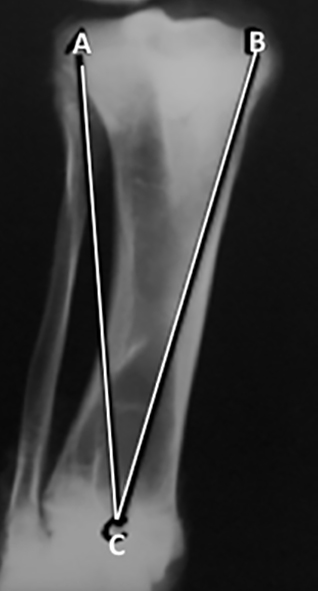

Se realizaron radiografías, antero-posterior y lateral de los fémures y las tibias, postmortem de los miembros inferiores. Las radiografías fueron medidas. En las radiografías antero-posterior del fémur se trazaron y midieron 6 líneas (Figura 1).

Figura 1: Radiografía de fémur antero-posterior. Líneas desde la punta del trocánter mayor. A-D: a la región más lateral del cóndilo lateral. A-E: al intercóndilo. A-C: a la región más medial del cóndilo medial.

(Figura 2): 1. A-D: desde la punta del trocánter mayor a la región más lateral del cóndilo lateral. 2. A-E: desde la punta del trocánter al intercóndilo. 3. A-C: desde la punta del trocánter a la región más medial del cóndilo medial. 4. B-D: desde el centro de la cabeza a la región más lateral del cóndilo. 5. B-E: desde el centro de la cabeza al intercóndilo.  6. B-C: desde el centro de la cabeza a la región más medial del cóndilo medial.

Figura 2:Radiografía de fémur antero-posterior. Líneas desde el centro de la cabeza. B-D: a la región más lateral del cóndilo. B-E: al intercóndilo. B-C: a la región más medial del cóndilo medial.